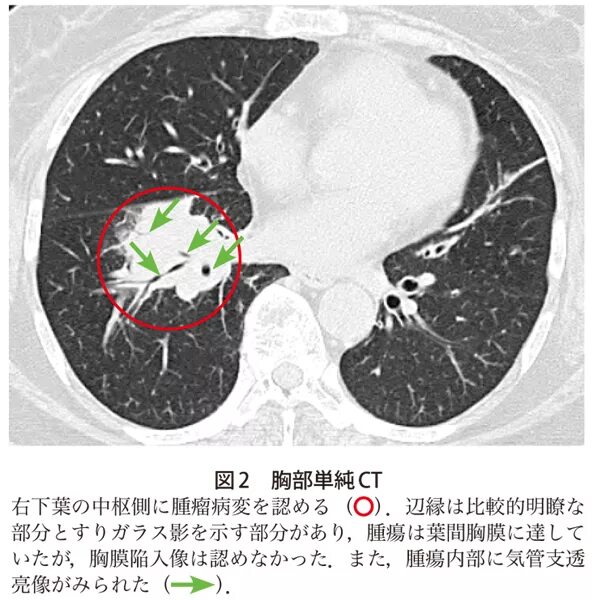

Ct search